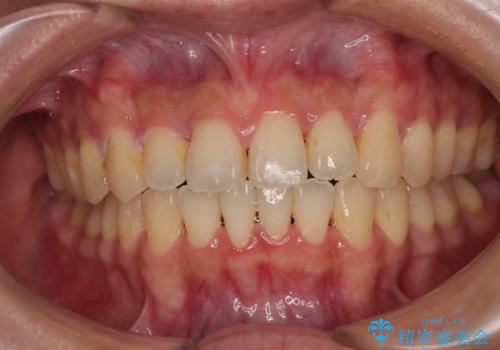

受け口と八重歯を改善 インビザライン矯正治療